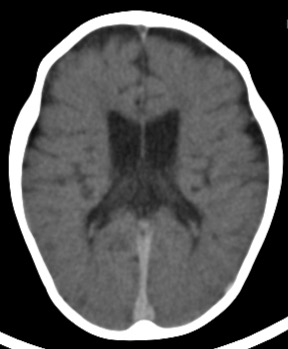

大脳半球の灰白質・白質コントラストは不明瞭

• 頭部は頭蓋内出血、頭蓋骨骨折は認めない。 両側大脳半球は萎縮している。びまん性、両側対称性で灰白質・白質ともに障害されているが、白質の萎縮がより顕著である。大脳半球の灰白質・白質コントラストは不明瞭。 萎縮の強い脳であり、生前も正常のコントラストはなかったのではないかと推測されるが、 死後変化も加わっていることは予測される。両側基底核は対称性に強く萎縮している。両側視床も対称性に萎縮しており、内側部分に高吸収化が目立つ。 以上の様な変化は、いずれも慢性の変化で、急性の変化が加わっていることを示す所見 は認められない。

• 静脈洞、大脳鎌、小脳テント、側脳室内脈絡叢の高吸収化が目立ち、血液就下によるものと考える。

• 頭蓋骨の縫合は透亮線として残っているが、年齢から考えると狭小化・不明瞭化してお り、脳萎縮による頭蓋骨早期閉鎖の発生を示唆している。